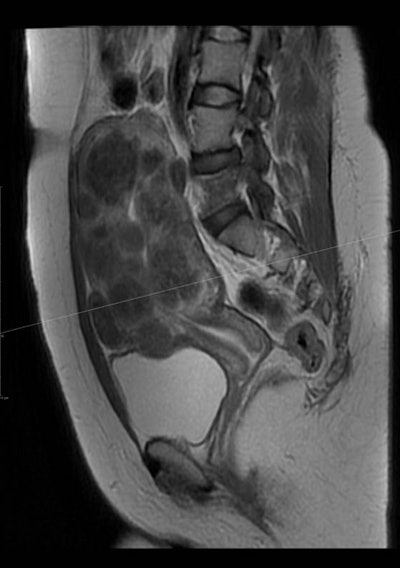

Uterine fibroids are benign tumors in the uterus that can cause prolonged, heavy menstrual bleeding that can be severe enough to cause anemia or require transfusion. Patients may also have disabling pelvic pain and pressure, urinary frequency, pain during intercourse, miscarriage, interference with fertility, and an abnormally large uterus resembling pregnancy.

The impact of uterine fibroids on pregnancy, the risk, and type of complications appear to be related to their size, number, and location. Certainly, infertility results when fibroids grow large enough that they obstruct one or both of the fallopian tubes. Additionally, fibroids are associated with a higher rate of miscarriage when they grow into the cavity of the uterus where embryos implant (i.e., submucus or intracavitary).

The minimally invasive interventional radiology procedure of uterine fibroid embolization (UFE) has a lower complication rate than myomectomy. It may be performed if a woman has a single fibroid, many fibroids, or large-sized fibroids and a gynecologist cannot rule out a hysterectomy during myomectomy, myomectomy is unsuccessful, or when fibroids recur after myomectomy. The procedure may also be performed for women who want to avoid surgical removal for culture reasons, surgically high-risk women with fibroids, women of any age with fibroids who want to preserve their uterus and avoid the psychological trauma of hysterectomy, and, more important, in unmarried virgin women with fibroids.